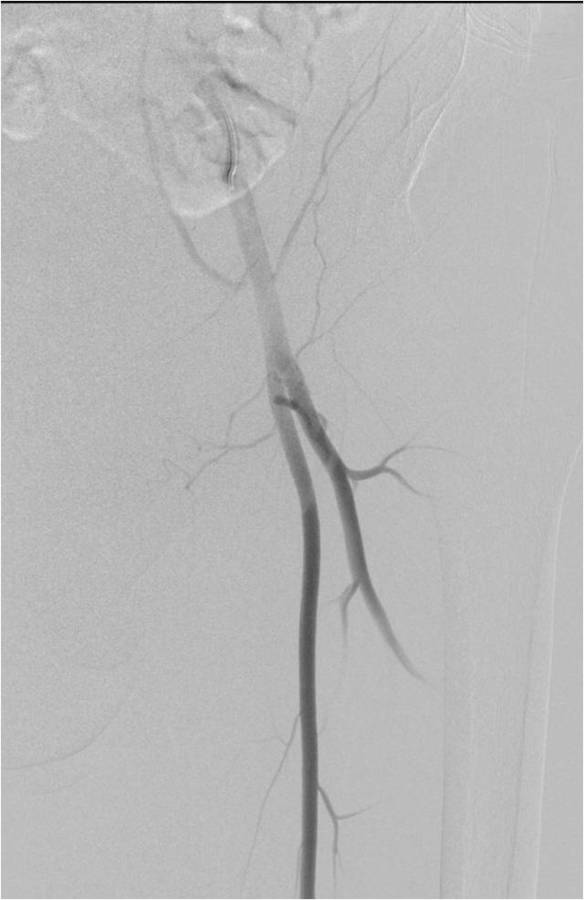

Physician Assistant Lower Limb and Thorax Written Examination - Radiology Pool

Gallery of Unlabled Radiographs from Lecture (Dr. French) - 2020

Click a thumbnail to enter the gallery display. Click the file name link at the bottom left of the gallery display to view the image at high resolution.